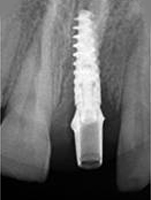

X-ray of Implant

Single Tooth Implant

X-ray of Implant + Abutment

X-ray of Implant +

Abutment + Prosthesis